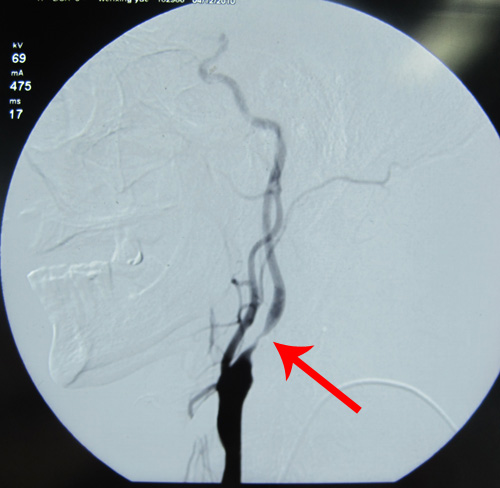

DSA示:左侧颈内动脉分叉部位重度狭窄,狭窄率约为80%。

左侧颈内动脉重度狭窄